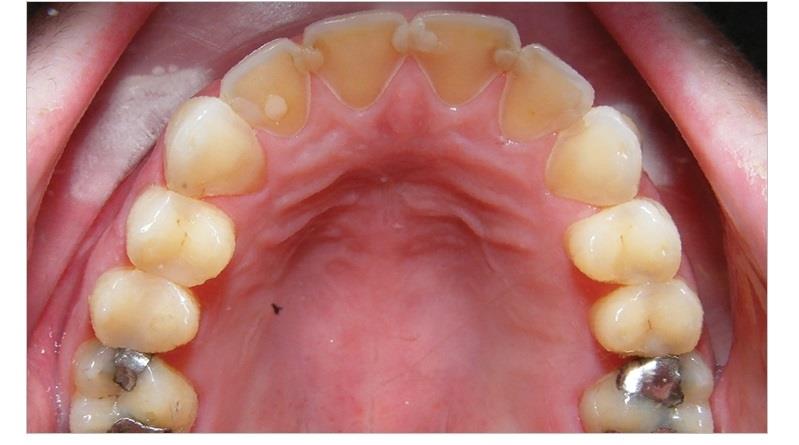

ومن الأعراض الجسدية، فقدان مينا الأسنان نتيجة للقيء المتكرر، المعاناة من الانتفاخ والإمساك، وانتفاخ الغدد اللعابية، واضطرابات في نظام القلب، وتمزقات في المريء، وشعور عام بالإعياء.